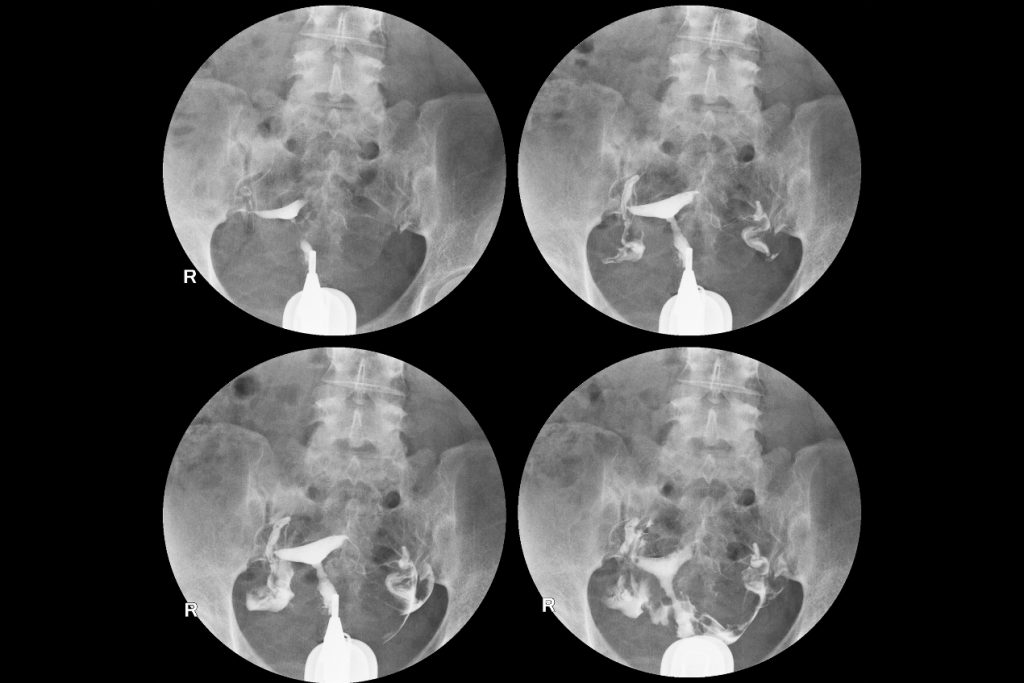

Badanie HSG, czyli histerosalpingografia, jest badaniem RTG, czyli rentgenowskim, którego celem jest dokładne sprawdzenie stanu macicy i jajowodów. Tak samo jak w przypadku innych badań rentgenowskich, żeby mieć możliwość dokładnego zobaczenia tego, na czym zależy lekarzowi, przed badaniem pacjentce podawany jest kontrast, który sprawi, że na wykonanych zdjęciach ginekolog będzie mógł dokładniej się przyjrzeć i ocenić kształt jamy macicy, kształt i drożność jajowodów, stan błony śluzowej macicy, a także stan przydatków.

Histerosalpingografia trwa zaledwie kilkanaście minut. Wykonuje się je w znieczuleniu, czasami nawet w znieczuleniu ogólnym. Pacjentka w trakcie badania przebywa na fotelu ginekologicznym, w takiej samej pozycji jak w trakcie kontrolnego badania ginekologicznego. Na początku lekarz zakłada wzierniki, a następnie wprowadza do środka przy użyciu aparatu Schultza środek kontrastujący. Pierwsze zdjęcia są wykonywane w momencie, w którym środek cieniujący wypełni już jamę macicy, kolejne, gdy dojdzie i wypełni jajowody, natomiast ostatnie, gdy zacznie wydostawać się do jamy brzusznej. Dokładna ilość wykonanych zdjęć zależy przede wszystkim od rodzaju wskazań i ewentualnych dolegliwości u pacjentki.